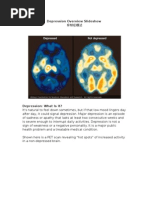

o Biochemistry: Differences in certain chemicals in the brain may contribute to

symptoms of depression.